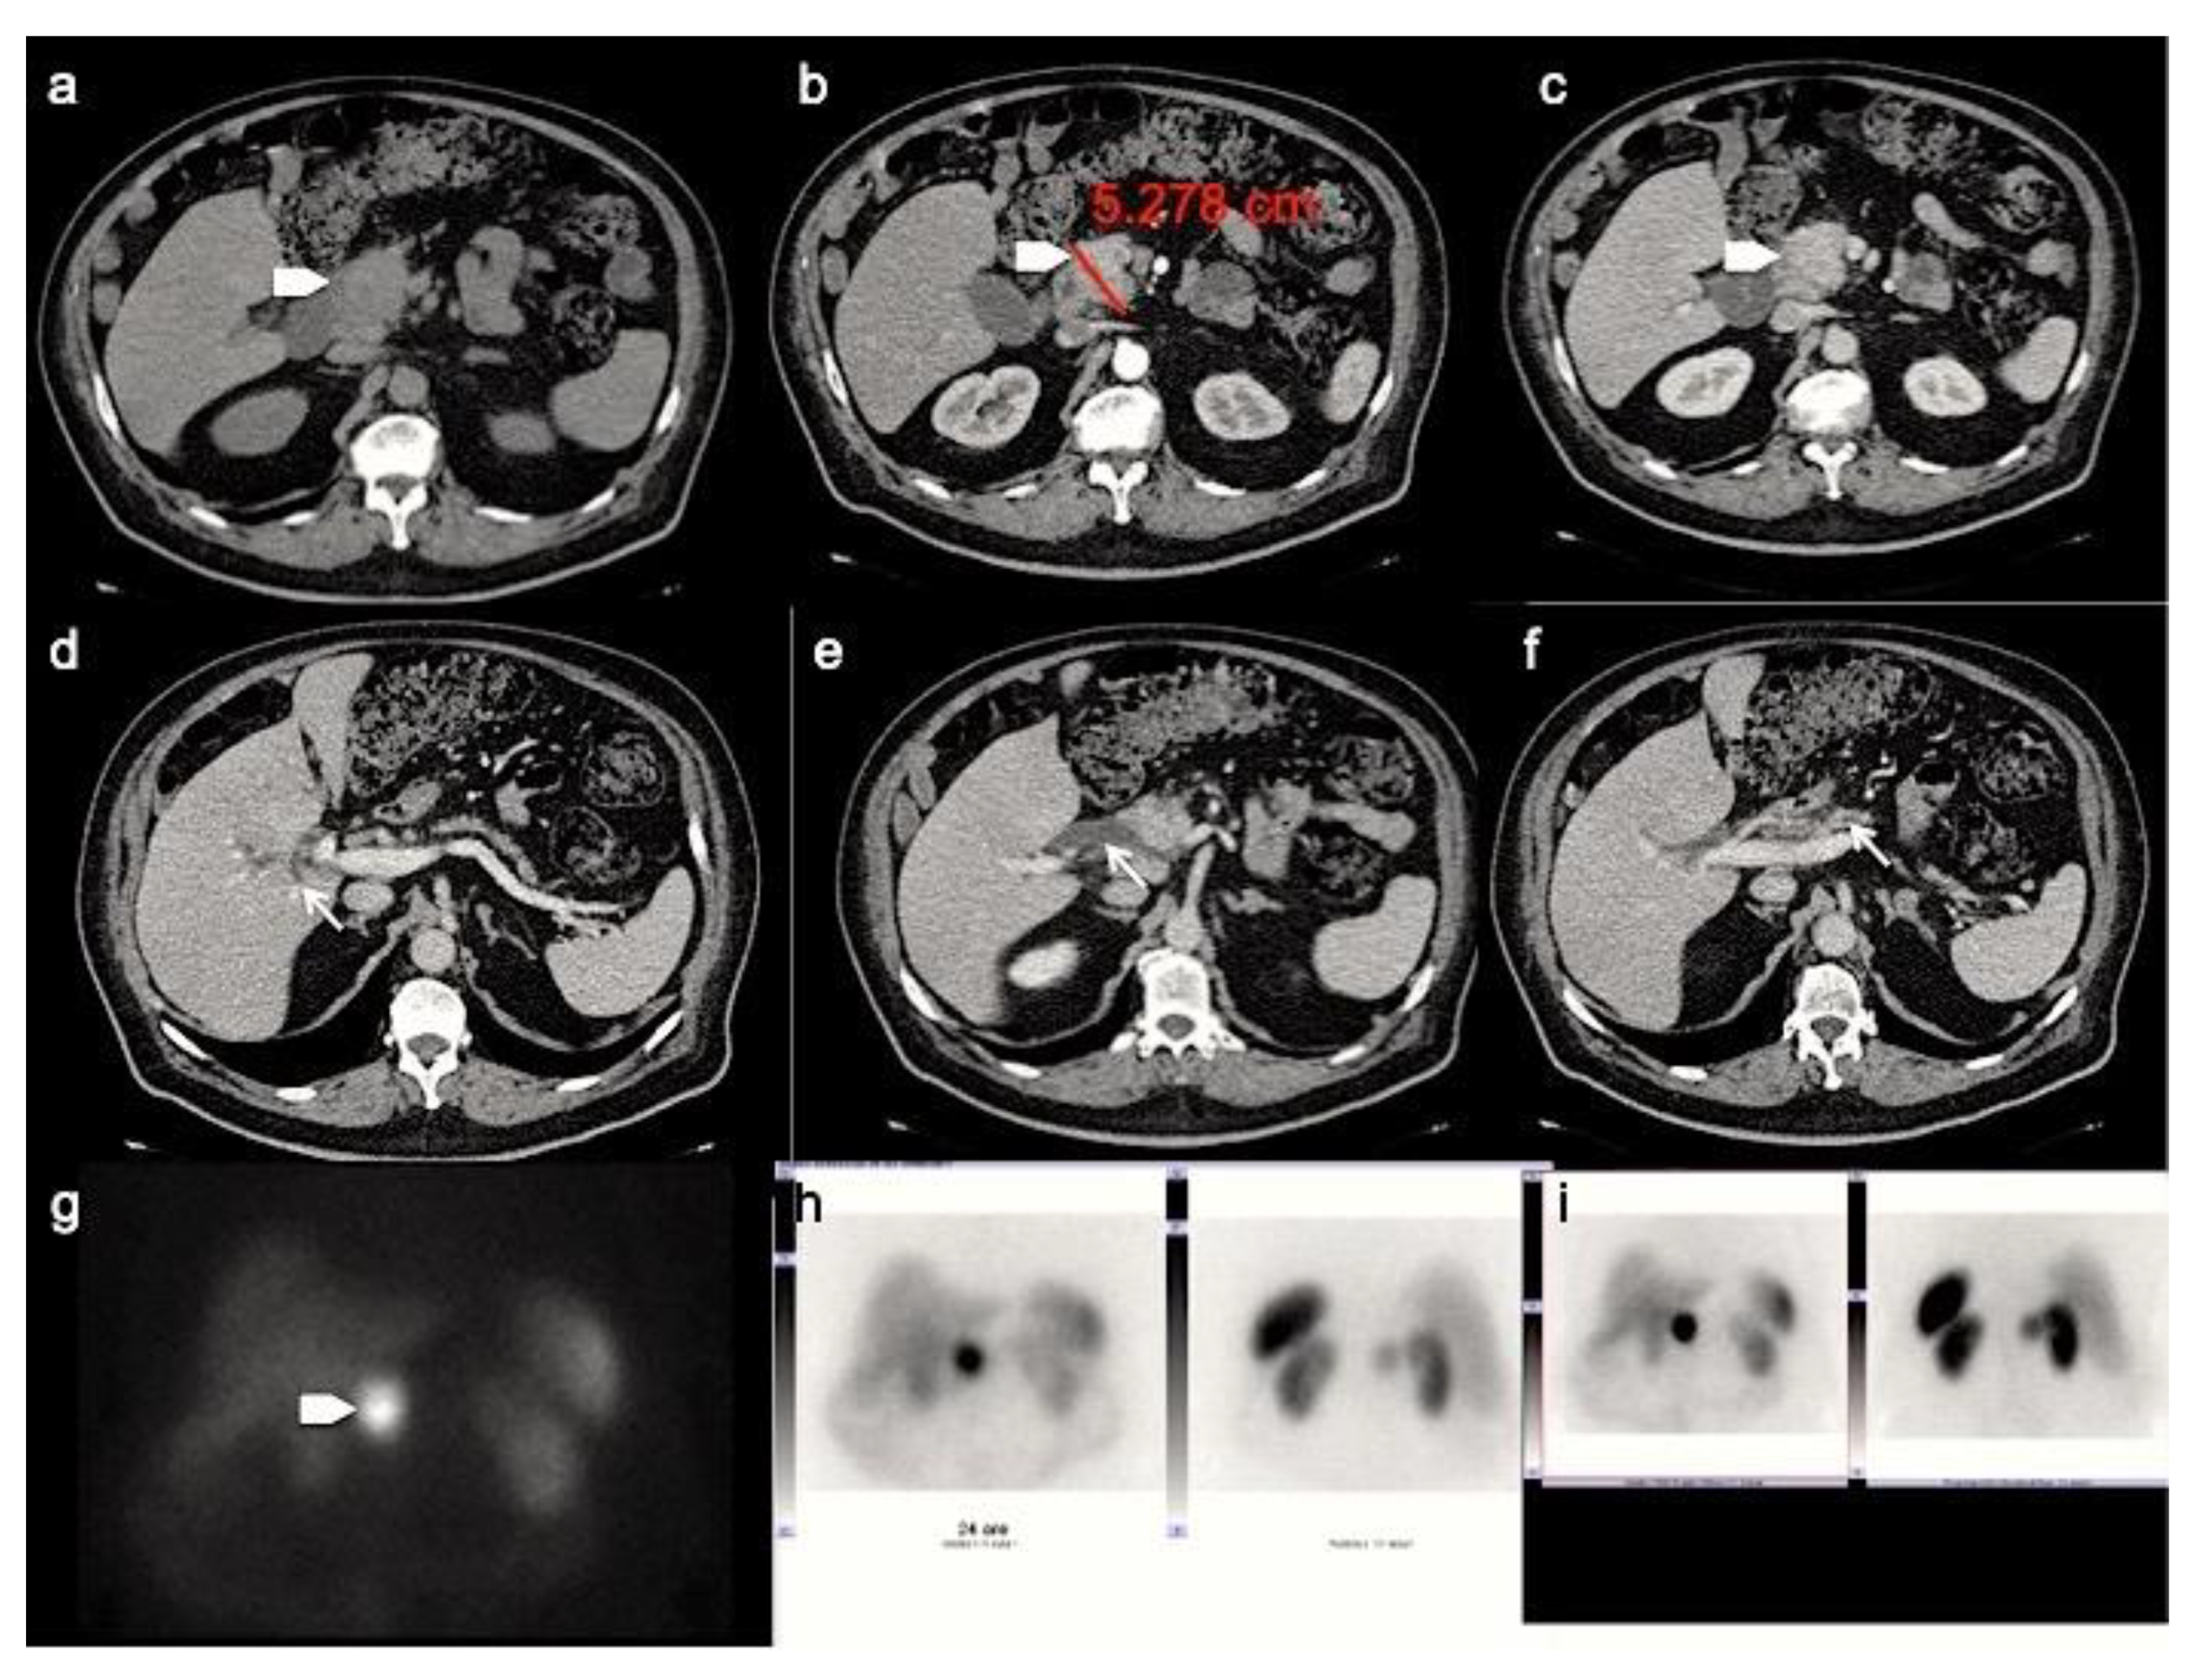

The most common atypical presentations are the hypo-enhancing pattern (Figure 2), the intra-vessels growth, the intra-ductal growth and the cystic and calcified variants, aspects that can make difficult the radiological differential diagnosis with pancreatic ductal adenocarcinoma [31]. Furthermore, as recently demonstrate by Kim. Et al., panNENs with uncommon findings are associated with a significantly worse survival rate [31].

Figure 2.

Patient with liver metastases from poorly differentiated pancreatic neuroendocrine carcinoma. CT images in the transverse plane during the basal (a), the arterial (b) and portal (c) phases show a large mass developed in the pancreatic tail with atypical hypo-enhancing pattern (arrow). This lesion is associated with multiple liver metastases (arrowheads) that appear hypodense with rim enhancement during arterial phase (b). According to the poorly differentiated tumor feature, FDG PET/CT (e,f) shows high uptake in pancreatic lesion while Somatostatin Receptor Scintigraphy with 111-pentetrotide is negative (d).

Analysis of pancreatic masses solely based on enhancement patterns can be misleading, as panNENs sometimes can have a highly fibrotic stroma and show slow and progressive wash-in. In a recent retrospective study by Jeon et al. on a population of patients with surgically confirmed panNETs, 49% showed a non-hypervascular pattern [32]. On the other hand, the main pancreatic ductal involvement, presenting with upstream duct dilatation, is infrequent, and is an independent predictor for adenocarcinoma [31]. However, in a recent study focused on the identification of CT features distinguishing panNECs from panNETs by Park HJ et al., the first ones demonstrated significantly higher frequencies of main pancreatic ductal dilatation (Figure 3) [33].

Figure 3.

CT images in the transverse plane during the basal (a), the arterial (b) and portal (c) phases show a large mass developed between the second portion of the duodenum and the pancreatic head (arrowhead). This panNEN is associated with a dilation of the intrahepatic biliary tree (d), common bile duct (e) and main pancreatic ductal (f) (arrows). Somatostatin Receptor Scintigraphy with 111-pentetrotide shows high uptake of somatostatin analogue in pancreatic lesion (g–i).